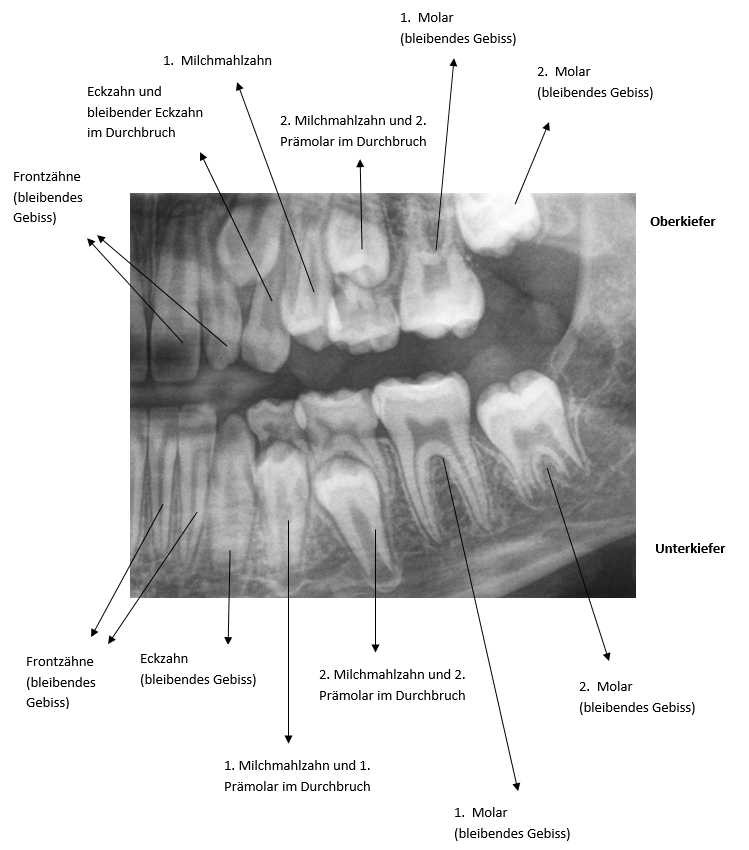

Source: halsternpag.pages.dev Wurzelbehandlung Zahnarzt Weiding Dr. Andreas Lozert , Lebensjahr) mit dem dadurch bedingten normalen Verlust der Milchzähne werden die Milchzahnwurzeln durch die nachdrängenden bleibenden Zähne resorbiert (aufgenommen) und scheinen keine Wurzeln (gehabt) zu haben. Warum haben Milchzähne keine Wurzeln? Beim Zahnwechsel (6

Source: sumakinggwp.pages.dev Vitalamputation eine Alternative zur Wurzelkanalbehandlung am Milchzahn Quintessenz VerlagsGmbH , Lebensjahr) mit dem dadurch bedingten normalen Verlust der Milchzähne werden die Milchzahnwurzeln durch die nachdrängenden bleibenden Zähne resorbiert (aufgenommen) und scheinen keine Wurzeln (gehabt) zu haben. Ist dies gefährlich? Oder wird der neue Zahn das Stück Wurzel mit hinausschieben?

Source: bcsossow.pages.dev Zahn Mit Wurzel Ausgefallen Captions Pages , Die Zähne bei Kleinkindern und Babys sind im Aufbau bereits denen eines Erwachsenen gleich. Lebensjahr) mit dem dadurch bedingten normalen Verlust der Milchzähne werden die Milchzahnwurzeln durch die nachdrängenden bleibenden Zähne resorbiert (aufgenommen) und scheinen keine Wurzeln (gehabt) zu haben.